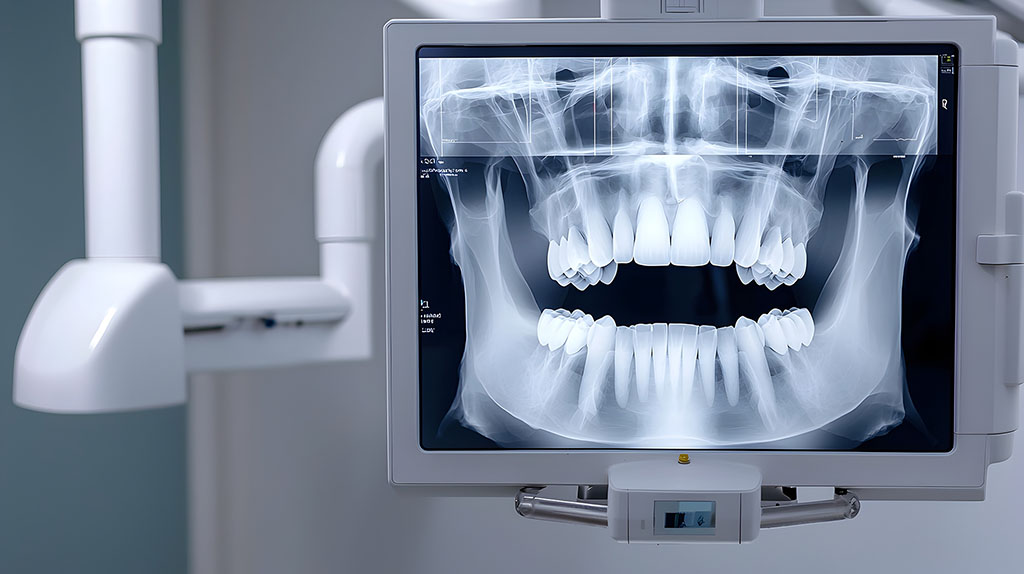

TAC Cone Beam: più chiarezza per il dentista, più tranquillità per te

Con la TAC Cone Beam ogni dettaglio della tua bocca viene rilevato in pochi secondi, senza fastidi né attese.

La tomografia computerizzata Cone Beam (CBCT) sfrutta un fascio di raggi X a forma di cono per generare immagini 3D ad alta risoluzione di denti, ossa e articolazioni.